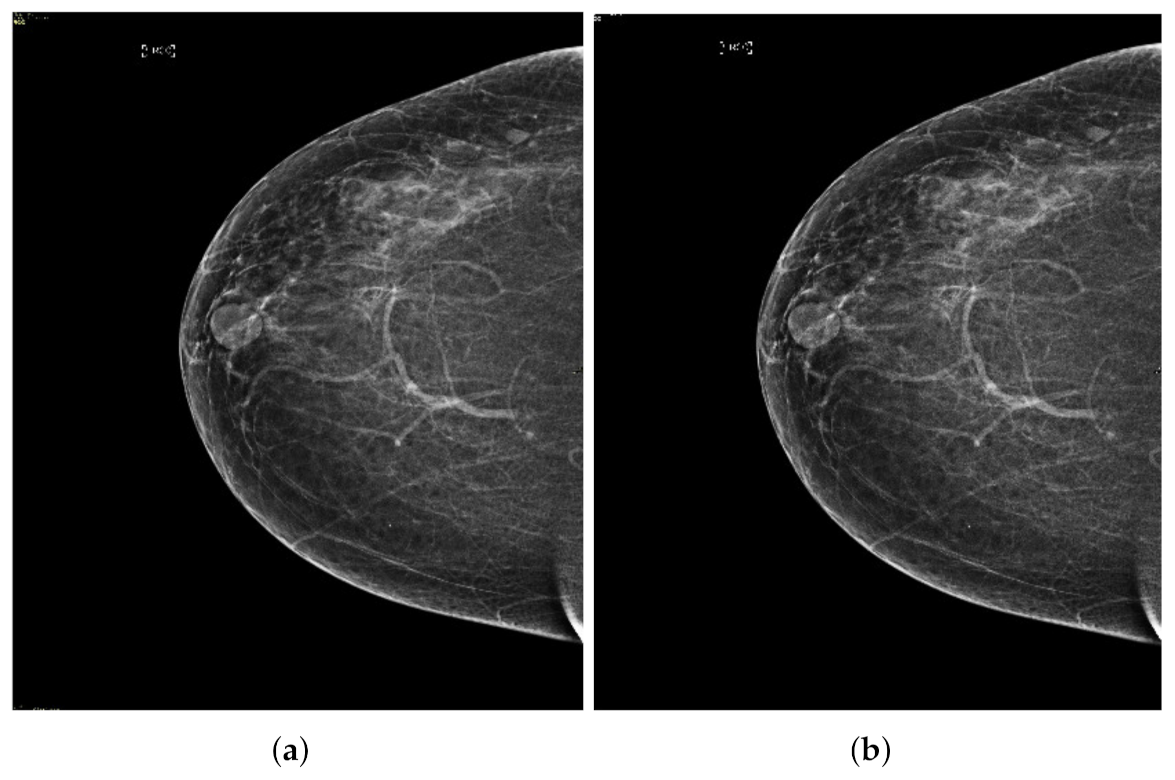

Figure 14.

Analysis of MLO view of BI-RADS-4 mammogram images.